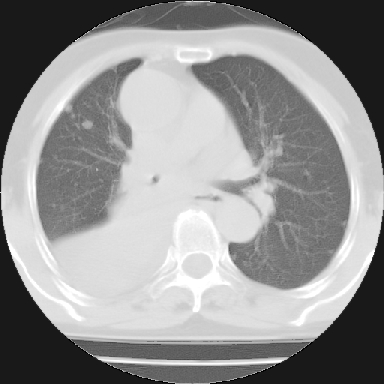

以下是引用苯小孩在2007-4-13 16:20:00的发言:[br]1、右下肺中央型肺癌并阻塞性肺不张、肺内转移、胸椎右侧附件亦有转移<横断层面第8层>.[br]2、右侧胸腔积液.

以下是引用swyyy2007在2007-4-13 15:31:00的发言:[br]右肺门下区肿块,右肺下叶支气管阻塞,右肺下叶不张,右侧大量胸腔积液,右肺中叶见结节状高密度影,边缘清,纵隔内见肿大淋巴结。首先考虑右下肺中心型肺癌伴右肺下叶不张、中叶、纵隔淋巴结转移。右侧胸腔积液。